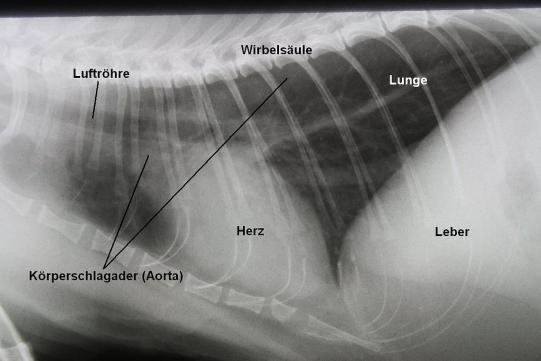

Zur genaueren Abklärung der Ursache für das Herzgeräusch werden Bruströntgen angefertigt und ein Herzultraschall durchgeführt.

Das Bruströntgen zeigt eine normale Herzsilhouette und ein normales Lungenfeld. Insbesondere sind keine Hinweise für die häufigste Katzen-Herzkrankheit (die hypertrophe Kardiomyopathie HCM) wie vergrösserte Herzvorhöfe zu finden.